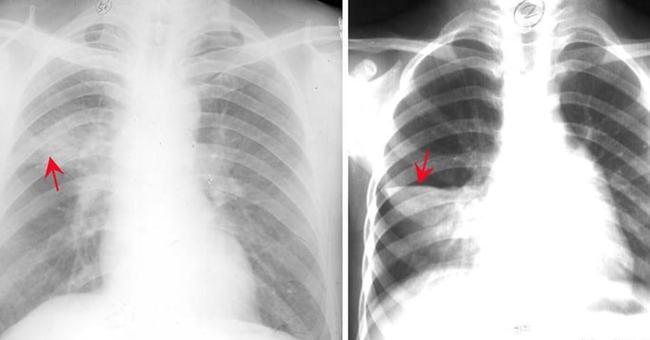

网易首页>正文申请入驻> 右肺中叶大叶性炎症胸部正侧位片:右肺中叶见

大叶性肺炎胸片

大叶性肺炎x线表现

大叶性肺炎影像